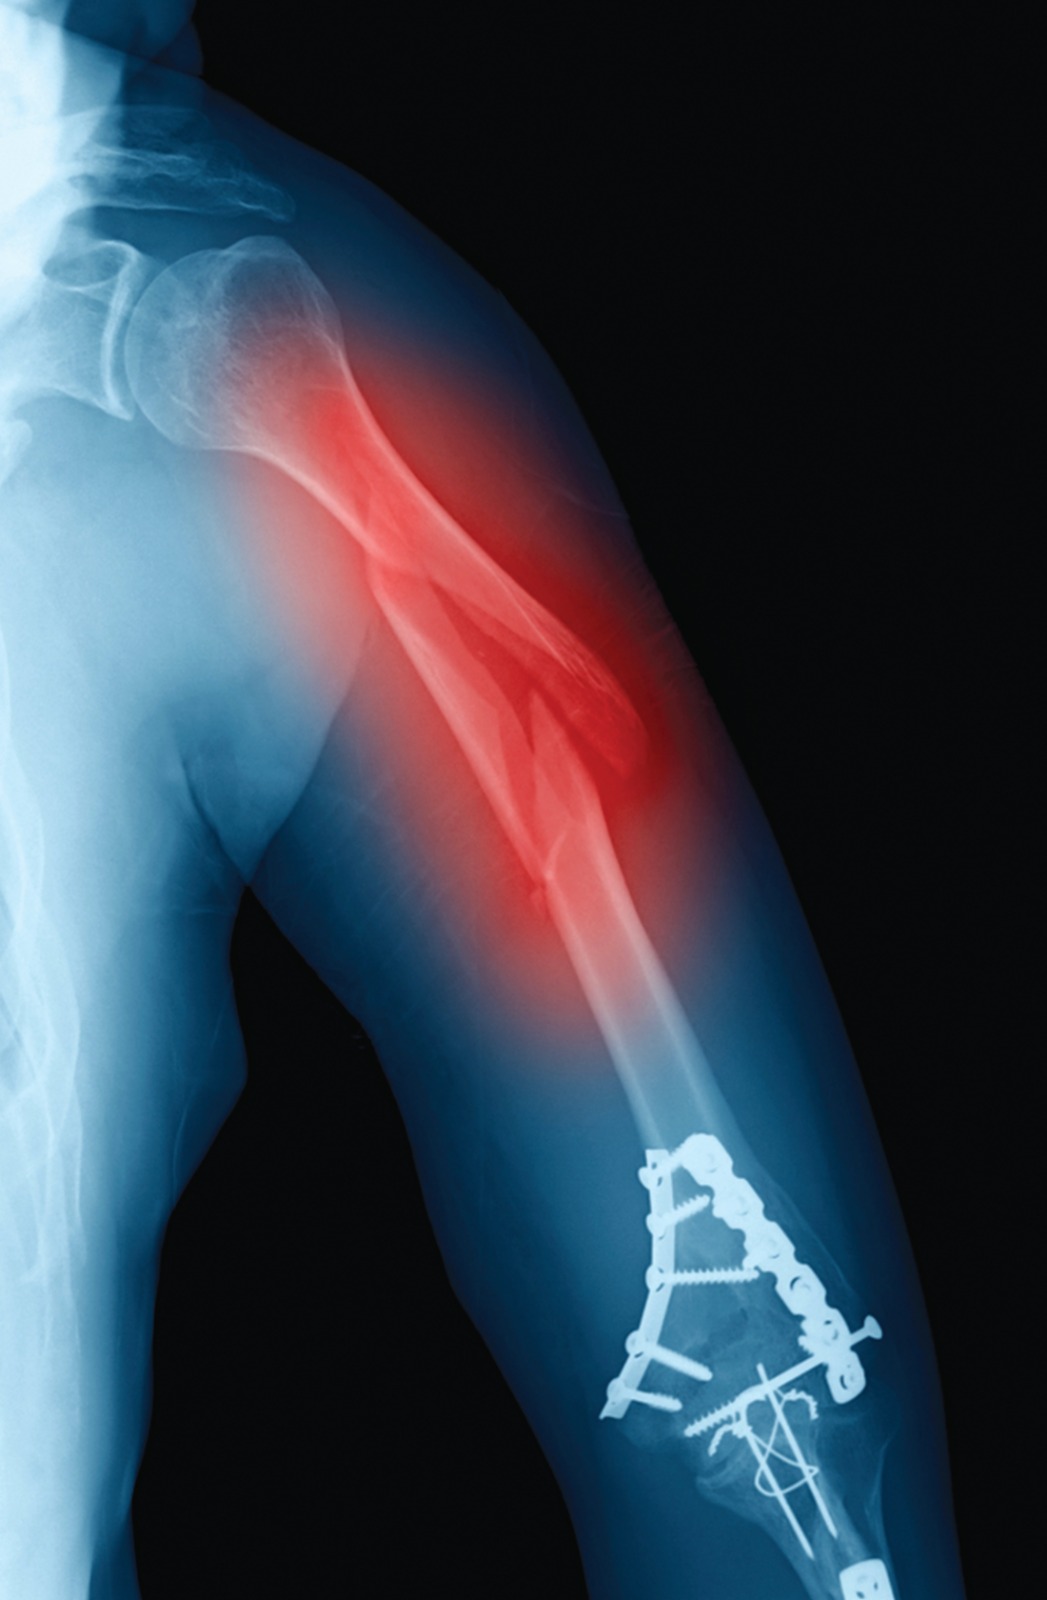

Clavicle fractures are a common type of fracture, accounting for 2.6% of all fractures and 5% of adult fracture1 Among clavicle fractures, middle-third fractures make up nearly 82% of cases.2 This is largely due to the unique structure of the clavicle, which is thinnest at the junction of the outer and middle thirds and lacks additional protection from muscles and ligaments.2,3 While there are several treatment options for clavicle fractures, the majority are traditionally treated non-operatively. However, due to its location, a clavicle fracture is often displaced, making non-surgical treatment challenging. Clavicle fractures can occur in people of all ages, but they are more common in children and young adults due to their active lifestyles.4,5 In adolescents, clavicle injuries are often caused by falls from height or participation in sports.5 A significant portion of fractures is also caused by high-energy injuries such as car accidents. There is a bimodal distribution of adult clavicle fractures, with a higher incidence in males under 30 years of age due to high-energy trauma and a second peak in the elderly population due to osteoporosis, which are typically associated with low-energy falls.6 Young adults tend to fracture the mid-shaft of the clavicle, while the elderly are more likely to fracture the lateral end.6 Displaced mid-shaft clavicular fractures, which occur in the middle part of the collarbone, can be treated with plate fixation, a surgical procedure in which a metal plate is attached to the bone using screws to hold it in place during healing. Some studies have suggested that plate fixation may lead to better functional outcomes, such as improved range of motion and strength, compared to non-operative treatment, which involves using a sling or other immobilization device to hold the bone in place while it heals. In the past, non-surgical treatment was preferred for mid-shaft clavicle fractures, even in cases of obvious displacement, due to a low rate of non-union.7,8 However, recent research has found that the nonunion rate of displaced fractures after non-surgical treatment is higher than previously reported. 9,10 There is currently a consensus on non-surgical treatment for mid-shaft clavicle fractures without displacement, but the optimal treatment for displaced mid-shaft clavicle fractures remains controversial. 11The goal of any clavicle fracture treatment method is to achieve bony union while minimizing dysfunction, morbidity, and cosmetic deformity. In non-operative treatment methods, the first step is always shoulder immobilization. This is typically achieved using a simple sling or a figure-of-eight brace. However, there is no clear indication of how long immobilization should be continued, as it can vary depending on the patient’s age and fracture details.11 After immobilization, the physician needs to reposition the fractured bone to its normal location, which becomes more difficult with more compound and displaced fractures. While the movement is generally discouraged, some physicians may recommend starting isometric physiotherapy and resistance exercises after 4-8 weeks of immobilization, depending on residual pain and discomfort. Non-operative treatment can be time-consuming, with complete union often taking 5-7 months. There are several surgical treatment options for clavicle fractures, including inter fragmentary screw fixation, intramedullary (IM) fixation, cerclage wiring, and plate fixation.12 The present study aims to evaluate the functional outcomes of plate fixation for the treatment of displaced mid-shaft clavicle fractures. Plate fixation is a type of internal fixation in which a plate made of surgical-grade stainless steel or titanium is attached to the fractured bone with screws. The plates may be removed in a subsequent surgical procedure. Plate fixation has been shown to significantly reduce the nonunion rate for various types of fractures.13 Plate fixation provides immediate rigid fixation, including rotational stability, which is favorable for early rehabilitation protocols and is technically less demanding. Plate fixation may be an effective treatment for displaced mid-shaft clavicle fractures because it allows the bone to heal in a more anatomically correct position, potentially improving the patient’s range of motion and strength. However, it is important to note that plate fixation is a major surgical procedure with risks and potential complications, including infection, nerve or blood vessel damage, and failure of the plate or screws. This study aims to determine whether the benefits of plate fixation for displaced mid-shaft clavicle fractures outweigh the risks compared to non-operative treatment methods.